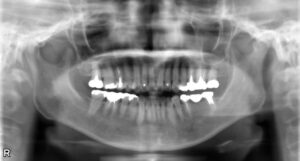

上下臼歯2本欠損症例

BEFORE AFTER 61歳女性/上下2本/インプラント埋込手術 【治療内容】 歯肉の腫れと痛みが主訴でご来院の患者…